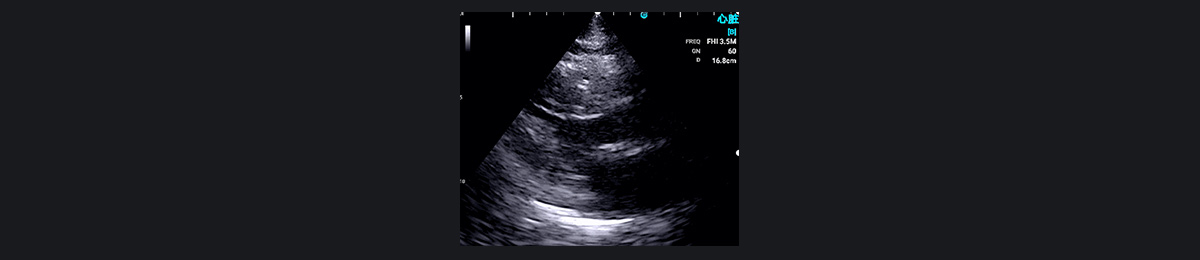

肥厚性梗阻性心肌病